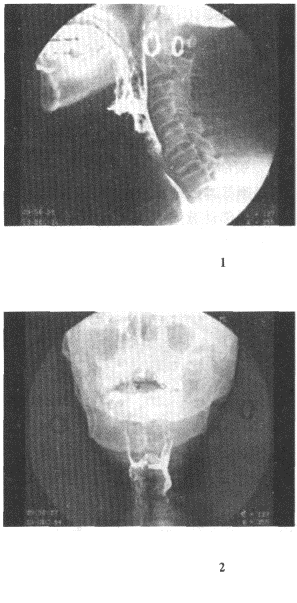

1.男,58歲,右頸部腫塊3個月,CT示右咽隱窩和咽鼓管閉塞,局部有軟組織密度腫塊,頸部淋巴結腫大,最可能的診斷是

正確答案:D 解題思路:鼻咽癌最好發于咽隱窩及咽鼓管,常有淋巴結轉移。